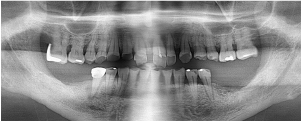

治療前のレントゲン

治療後のレントゲン

歯肉退縮により、以前他院で製作されたセラミック冠の審美障害があります。また時々、根元が腫れていたとのこと。前歯4本すべて根管治療を行い、ファイバーコアを入れてからオールセラミック(e-max)で修復しました。術後のレントゲンでは根尖性歯周炎が改善しています。